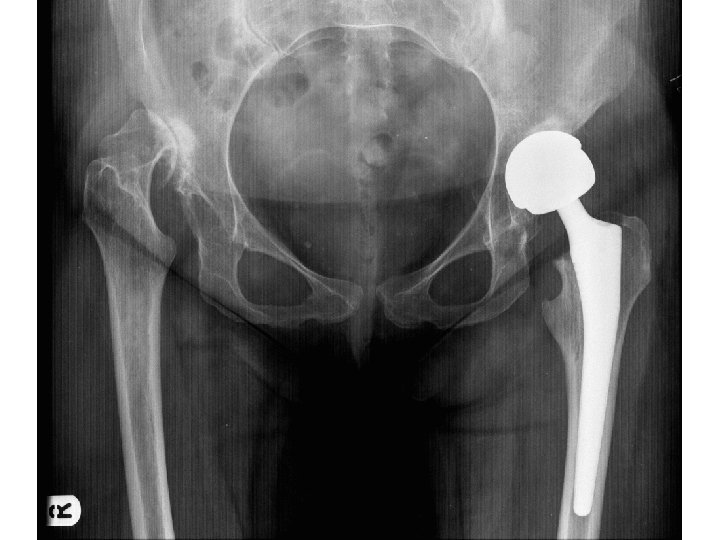

Treatment outcome Late Presentation > 1. 5 years Open reduction, capsulorrhaphy & Salter osteotomy(JBJSAm

Treatment outcome Late Presentation > 1. 5 years Open reduction, capsulorrhaphy & Salter osteotomy(JBJSAm 2007) 54 % hip survival at 45 years